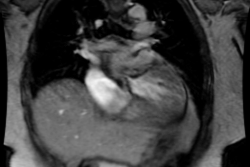

1- Bland-White-Garland

Syndrome: Anomalous origin of the left coronary artery (LCA)

from the pulmonary artery is a rare congenital anomaly accounting

for only 0.25-0.5% of all congenital heart defects [5,13]. It is

most commonly an isolated defect, but in 5% of cases it may be

associated with other cardiac anomalies (such as ASD, VSD, and

aortic coarctation) [5]. Prior to one

month of age, physiologic pulmonary hypertension tends to preserve

antegrade flow in the left coronary

artery [5]. However, ischemia can still occur due to the low

oxygen saturation within the pulmonary artery and low perfusion

pressure [7]. Symptoms generally occur in infants after they are

1-2 months old (other authors indicate symptoms start in the first

few weeks of life and become more severe as pulmonary vascular

resistance falls [13]) due to reversal/retrograde flow in the LCA

(left-to-right shunting) with resultant left ventricular

myocardial ischemia, infarction, LV failure, or dysrhythmia [5,7,15].

As the pulmonary resistance falls, blood flows from the aorta to

the RCA, through coronary-coronary collaterals to the LMCA, and in

a retrograde fashion into the pulmonary artery (stealing blood

from the myocardium) [13].

Infants typically present with failure to thrive, profuse sweating, dyspnea, and pallor [8]. The condition is one of the common causes of myocardial infarction and dilated cardiomyopathy in infants [7]. Without treatment, this anomaly most commonly results in death during early infancy (mortality rates of greater than 90% in the first year of life [7,15]), but survival into adulthood can occur if collateral coronary flow via the RCA is sufficient [8]. However, the risk for sudden cardiac death due to ischemic malignant ventricular dysrhythmia exits even in asymptomatic adult patients (sudden cardiac death occurs in 80-90% of cases) [5]. Treatment is surgical repair [5]- in infants this is done preferably using the coronary button transfer that produces the most anatomic correction and has excellent long-term results [8]. In adults, the preferred method is ligation of the LCA at its origin form the PA and placement of a CABG using the internal mammary artery or a saphenous vein graft [8]. In this syndrome, the LCA typically arises from the left inferolateral aspect of the main pulmonary artery just beyond the pulmonary valve [8].

Patients are generally noted to have an anterior wall ischemic perfusion defect and mitral insufficiency. An inferior/posterior perfusion defect may also be seen secondary to a right coronary artery to left coronary artery to pulmonary artery shunt.